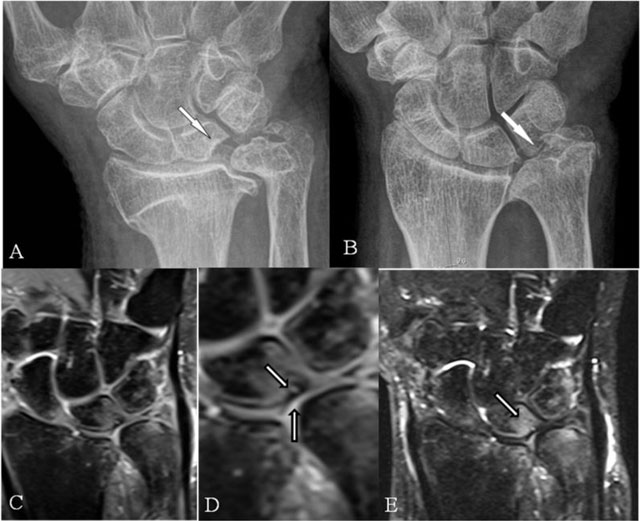

Figure 8

Scapholunar and lunotriquetral abutment. (A) PA plain radiograph; (B) Coronal SE PD-WI FS; (C) Coronal SE T2-WI FS; (D) Coronal 2D-GRE; (E) Coronal SE T2-WI FS; and (F) PA plain radiograph. (A) Widening of the scapholunate joint space on a Schneck I view. (B) Tear of the scapholunate ligament. (C) Juxta-articular subchondral band shaped marrow oedema. (D) Tear of the lunotriquetral ligament. (E) Juxta-articular band shaped kissing marrow oedema. (F) Massive deformation at the triquetral bone (other patient).

Scapholunar abutment

On radiographs (Figure 8A), a widened joint space (≥3 mm) [16] in rest or under stress (Schneck view) may be observed. MRI may show the ligamentous tear (Figure 8B) and the juxta-articular band shaped BMO (Figure 8C).

Lunotriquetral abutment

MRI may also show this ligamentous tear (Figure 8D) and the band-shaped BMO (Figure 8E). Eventual concurrent extrinsic ligamentous lesions should be looked for, as it is questionable if this solitary lesion results in abnormal mobility [17]. Due to chronic impaction, massive deformation may appear on radiographs (Figure 8F).